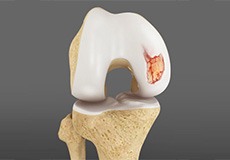

Osteochondral Defect of the Knee

An osteochondral defect, also commonly known as osteochondritis dissecans, of the knee refers to a damage or injury to the smooth articular cartilage surrounding the knee joint and the bone underneath the cartilage. The degree of damage may range from a rupture of the cartilage to a slight crack of the bone to a piece of the bone breaking off within the joint.

Chondral or Articular Cartilage Defects

The articular or hyaline cartilage is the tissue lining the surface of the two bones in the knee joint. Cartilage helps the bones move smoothly against each other and can withstand the weight of your body during activities such as running and jumping.